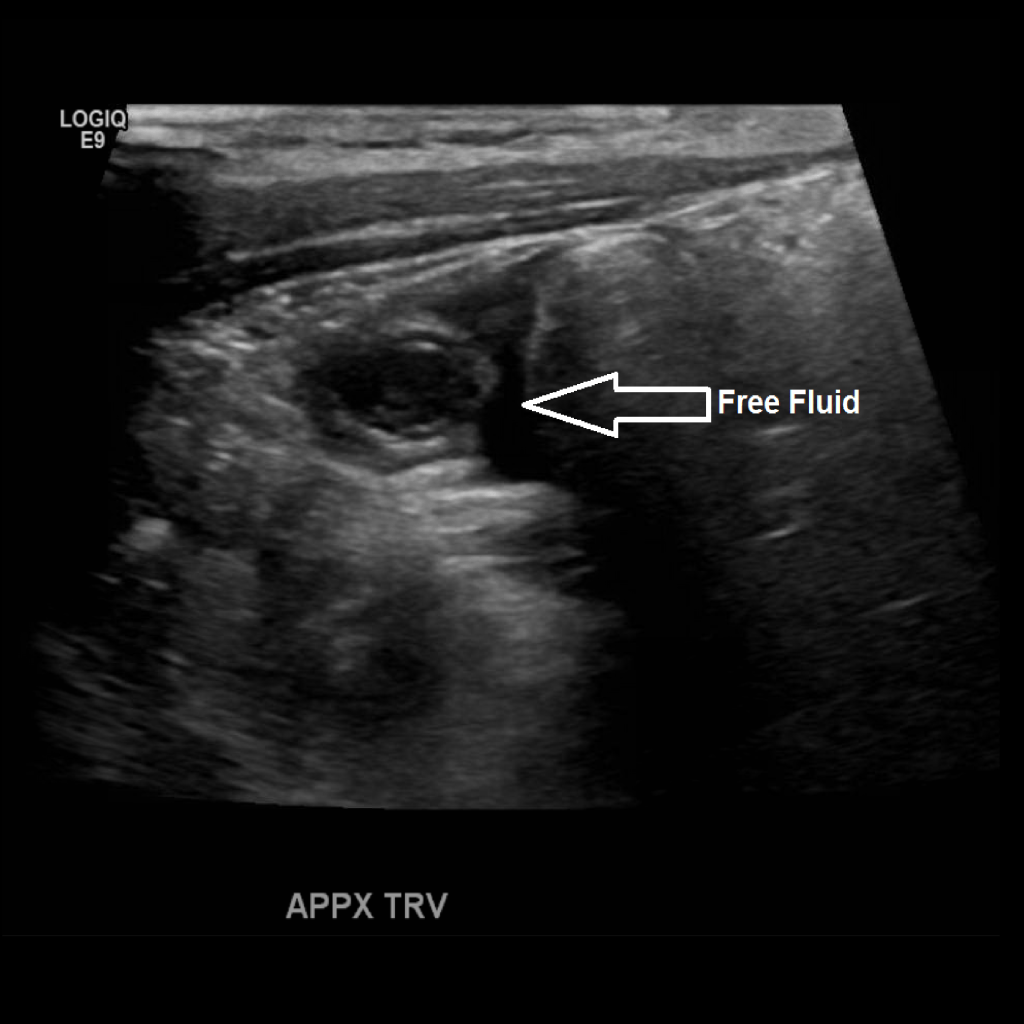

Appendicitis 12

0.9 cm positive appendicitis, with peripheral free fluid, and fat stranding.